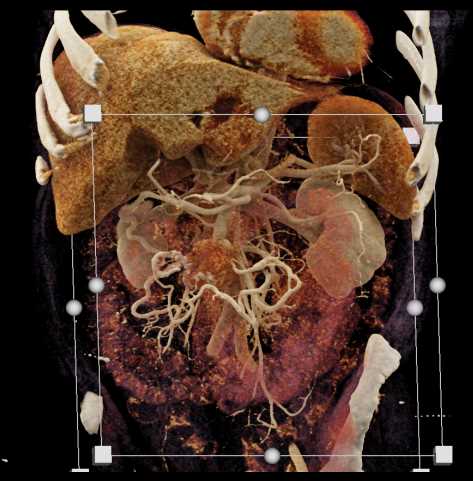

CT appearances and findings are the primary objective for radiologists to determine the accurate diagnosis during reading scans while considering patients' clinical presentation.

This section provides CT appearance for major organ systems and their common malignancies for the radiologists' convenient access that are supplemented with related pearls and lectures from CTisus to enhance radiologists' knowledge for each pathology.

View moreAccess over 322,000 CT Scans and the diagnosis that is identified for each case. The case studies range from CT Scans, MRI, and X-Rays, and are organized by anatomical region: Cardiac, Pancreas, Pediatric, Vascular, Gastrointestinal and more.